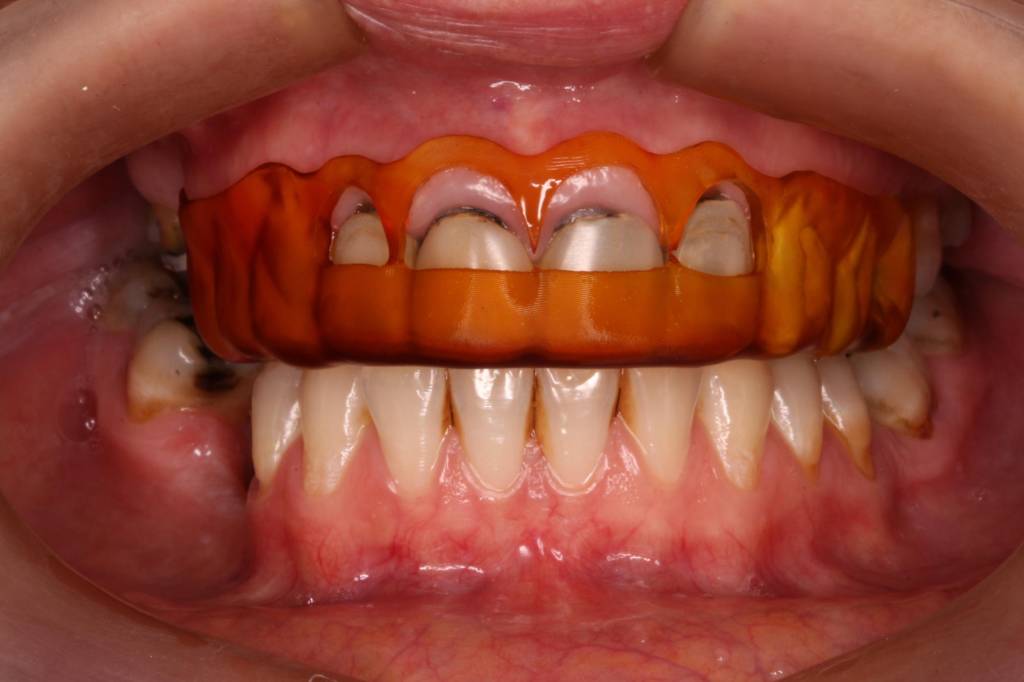

Los procedimientos quirúrgicos pueden ir desde extracciones simples hasta procedimientos más complejos. Entre ellos se incluyen la extracción de terceros molares (muelas de juicio), caninos retenidos, cirugías pre protésicas —necesarias para preparar la boca antes de una rehabilitación protésica— y cirugías periodontales destinadas a mejorar la salud de las encías.

En nuestro consultorio contamos con un especialista altamente capacitado para realizar todo tipo de cirugías dentales. Nuestro enfoque se basa en la utilización de técnicas mínimamente invasivas, que reducen el trauma quirúrgico, aceleran la recuperación y ofrecen una experiencia más cómoda para el paciente. Gracias al uso de tecnología digital avanzada y, en los casos que lo requieren, guías quirúrgicas personalizadas, logramos procedimientos más rápidos, precisos y seguros.

Cada cirugía comienza con un diagnóstico detallado mediante estudios radiográficos y, cuando es necesario, tomografías digitales que nos permiten planificar el procedimiento con exactitud. Esto no solo optimiza los resultados, sino que también reduce la posibilidad de complicaciones y mejora el postoperatorio.